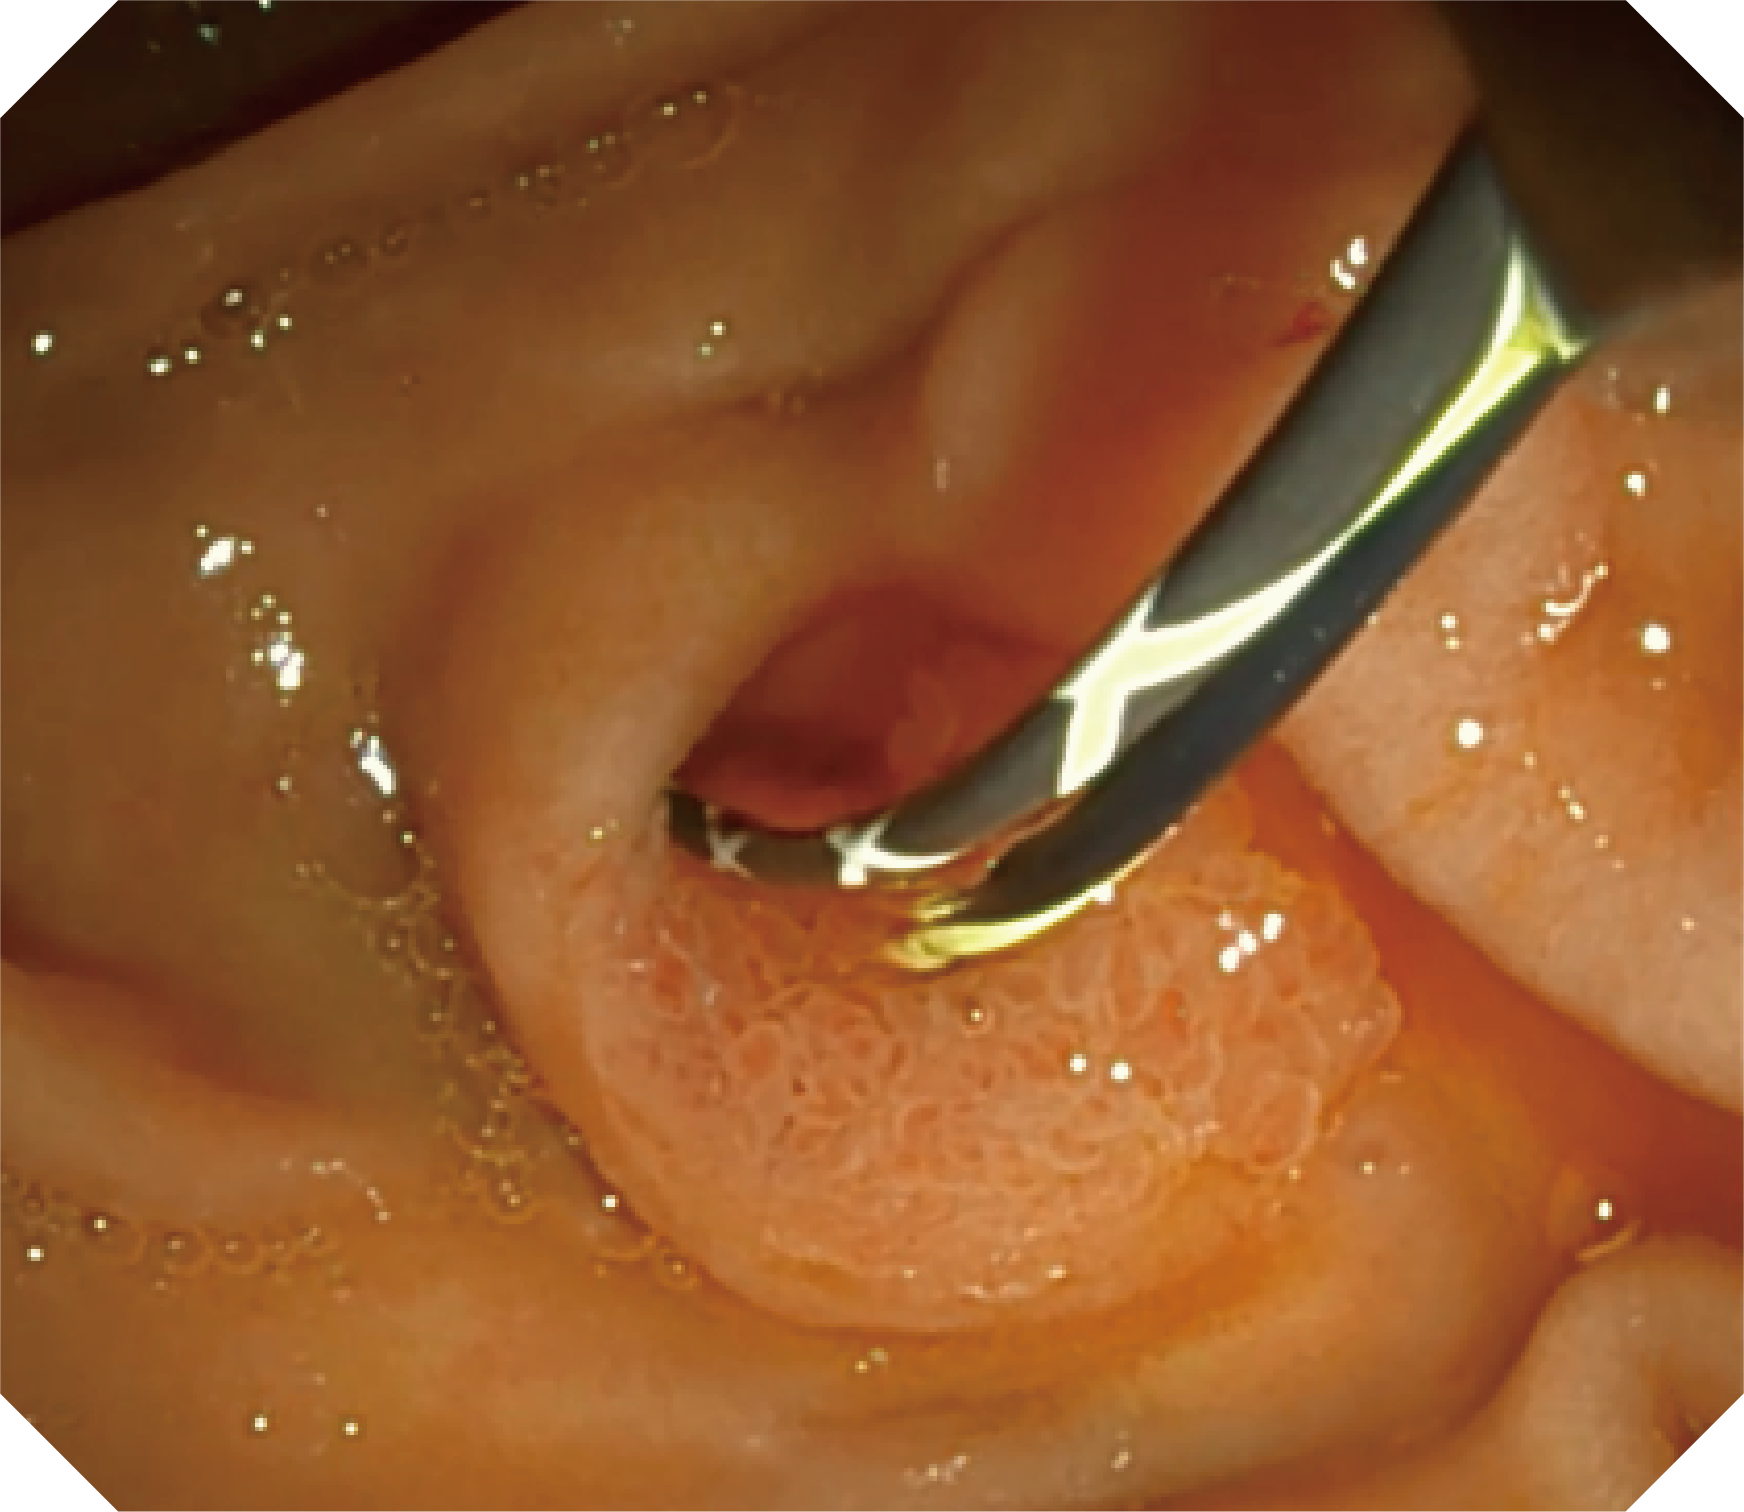

优异的手术器械抬举性

当切开刀伸出视野外时,导向面引导其回归视野